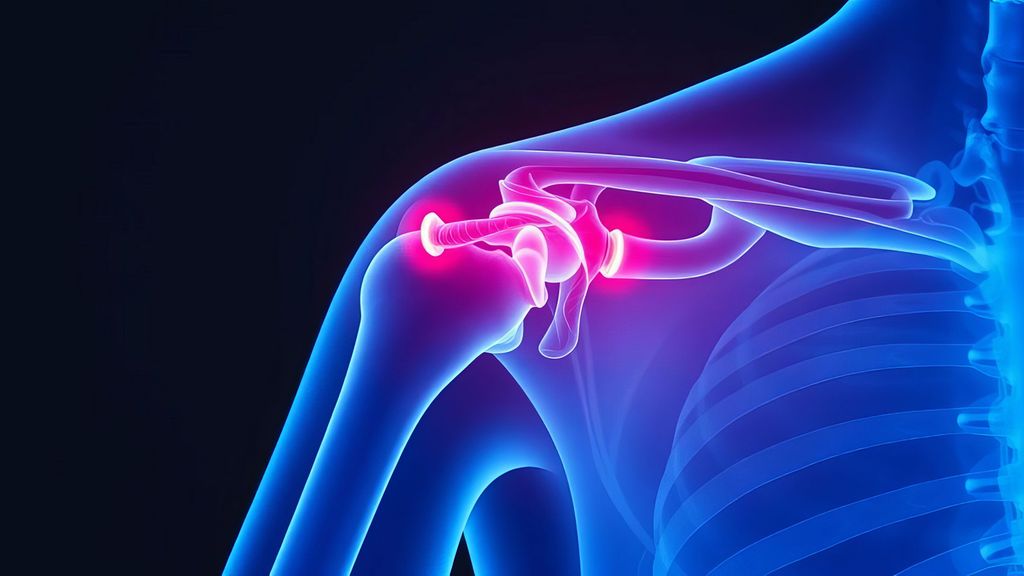

Hochgradige ACG-Luxationen – wann konservativ behandeln, wann nicht?

Verletzungen des Akromioklavikulargelenks (ACG) gehören zu den häufigsten Schulterverletzungen bei jungen und aktiven Menschen, insbesondere auch aufgrund der zunehmenden Beliebtheit von Risiko- und Kontaktsportarten. Die aktuelle Literatur zur Therapie der Akromioklavikulargelenksluxationen (ACG-Luxationen) zeigt allerdings noch immer eine uneinheitliche Herangehensweise, die sowohl konservative als auch operative Behandlungsmöglichkeiten berücksichtigt.1,2

Die aktuelle Literatur unterstreicht die Bedeutung der konservativen Therapie auch bei höhergradigen ACG-Verletzungen. Die Indikationsstellung sollte nicht nur auf dem Röntgenbild basieren, sondern auch individuelle Patientenfaktoren und funktionelle Einschränkungen berücksichtigen. Selbst nach einem initial konservativen Vorgehen kann bei Bedarf eine erfolgreiche operative Therapie durchgeführt werden. Trotz der umfangreichen Forschung gibt es noch keinen eindeutigen Goldstandard für die Therapieentscheidung bei ACG-Luxationen. Weitere Studien sind erforderlich, um die optimale Behandlungsstrategie für verschiedene Patientengruppen und Verletzungsgrade zu definieren.